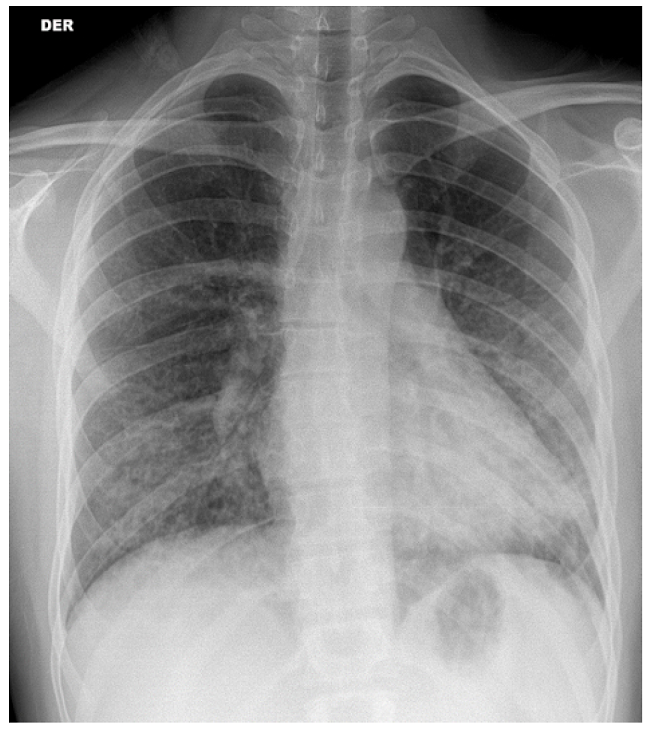

El paciente se controla con medico particular, quien indica estudio básico por sospecha de patología tiroidea; de manera incidental, en radiografía de tórax antero-posterior y lateral se pesquisa patrón de infiltrado bilateral intersticial, el cual es interpretado como neumonía atípica por patrón en la imagen y tos crónica. Los laboratorios son normales al inicio del cuadro clínico, por lo que se amplía estudio por sospecha de inmunosupresión y se inicia tratamiento con levofloxacino 500mg vía oral una vez al día por patrón dudoso de infiltrado bilateral (Figura 1).

El sujeto es hospitalizado para tratamiento; al examen físico se evidencia enflaquecido, anictérico y afebril y al examen pulmonar se auscultan sibilancias espiratorias difusas, sin uso de musculatura accesoria, pero disneico y con apremio respiratorio pese a saturación de 98% ambiental. Durante la estancia, se recaba antecedente de al menos 3 meses de disfagia lógica con tos en acceso de predominio nocturno asociado a baja de peso. Dentro de la historia destaca antecedente de relación homosexual de larga data sin protección y sin conocimiento de serología de su pareja. Al analizar la radiografía, el patrón radiológico evidencia neumonía por Pneumocystis jirovecci (Figura 1), por lo que se decide ampliar estudio serológico para VIH, sífilis y virus hepatotropos, destacando positivo para citomegalovirus (Tabla 2).